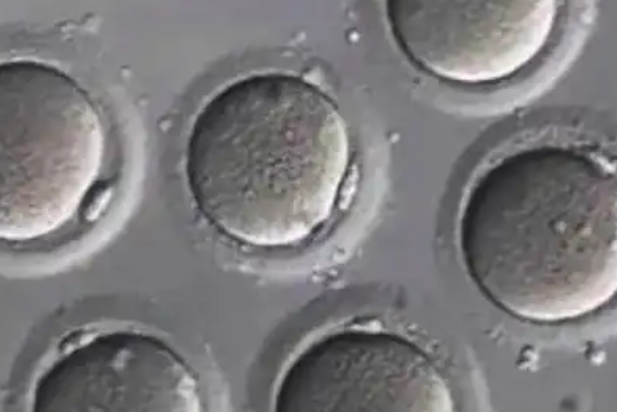

冷冻卵子

冷冻卵子将成熟卵母细胞冷冻后置于超低温环境达到保存生育能力目的的技术,好处时保留生育能力、减少生育风险。其费用通常在3000元左右一年,首次储存时还有身体检查以及取卵费用。在冷冻卵子前,需要对冻卵人士的年龄、身体健康状况、是否存在疾病等情况进行检查,目前最长冷冻时限已经超过了20年。